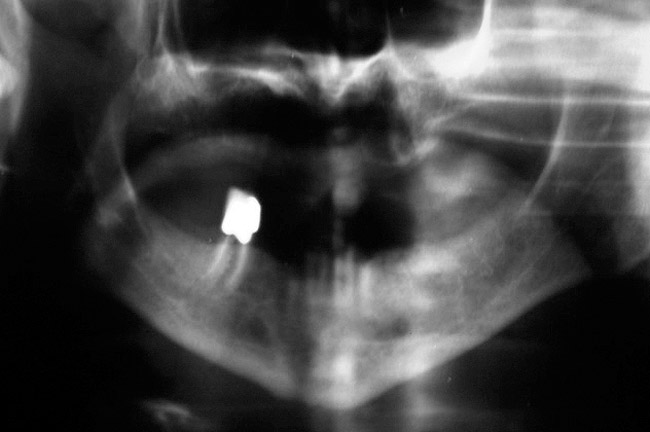

As stated earlier, spontaneous osteonecrosis is also possible. Figure 14 shows a case of spontaneous BRONJ resulting from wearing an ill-fitting denture. The patient had noticed the foreign material, but chose not to act on it. When the material was removed in the dental office (Figure 15 and Figure 16), blood streamed from the nose so severely that the patient had to be sent to an ear, nose, and throat (ENT) physician. The ENT took a computed tomography scan, which showed a large radiolucency in the upper left quadrant where the foreign material once had been (Figure 17). A review of the radiograph (Figure 18) showed that bone in the maxillary arch had decreased mineral density compared with the mandible. The biopsy report found necrotic bone with organisms consistent with actinomyces. These findings were consistent with biopsies found in the literature.22 When the patient returned for a 1-week follow-up, she still had signs of infection and the site had a foul odor and a discharge (Figure 19). The patient was informed that she should follow up with the ENT and return to the dental office after the infection had been resolved.

Figure 18  Panoramic radiograph showing decreased bone density.

Figure 18